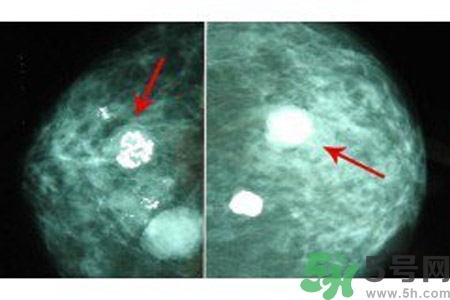

鈣化形態(tài)對辨別病變的良惡性有較大的意義,在觀察中發(fā)現(xiàn)。

顆粒狀、蛋殼狀、不規(guī)則團(tuán)塊狀及軌道狀鈣化多發(fā)生于良性病變。

針尖狀、小桿狀、分叉狀及泥沙樣鈣化多發(fā)生于惡性病變,鈣化的形式多樣、大小差異很大時,惡性的可能性越大,單純出現(xiàn)一種形態(tài)的鈣化時,成簇的針尖狀、分叉狀鈣化,對診斷惡性病變的意義較大。而單純出現(xiàn)泥沙樣鈣化,對病變的良惡性判別則比較困難。泥沙樣鈣化為不確定性鈣化,良惡性有重疊,但如果泥沙樣鈣化伴有其他鈣化形式,提示惡性病變。

乳腺鈣化數(shù)目

良性鈣化一般數(shù)目少,顆粒粗大。惡性病變表現(xiàn)為數(shù)目多,甚至無法計數(shù),如泥沙樣鈣化、成簇的針尖樣鈣化。但有時也可表現(xiàn)為數(shù)量較少,數(shù)顆或數(shù)十顆,數(shù)目少的惡性鈣化常見于分叉狀、小桿狀。1972年Woife提出15~20個/cm2個鈣化點(diǎn),即可判斷為惡性鈣化。

乳腺鈣化與腫塊的關(guān)系

鈣化可與腫塊并存,也可獨(dú)立存在;既可發(fā)生在病變內(nèi),也可獨(dú)立于腫塊之外。90%的導(dǎo)管原位癌是通過X線鉬靶照片發(fā)現(xiàn)的,且僅以乳腺內(nèi)鈣化作為惟一的表現(xiàn)形式。這是由于原位癌中央發(fā)生不規(guī)則壞死引起的鈣鹽在導(dǎo)管內(nèi)沉積或腫瘤細(xì)胞分泌而呈形態(tài)各異的的表現(xiàn)。